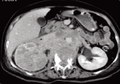

上腹部断层解剖第一层左上图中的阿拉伯数字提示“肝段”1、肝右叶;2、腹外斜肌;3、下腔静脉;4、肝尾状叶;5

消化疾病想掌握,腹部CT要看透!